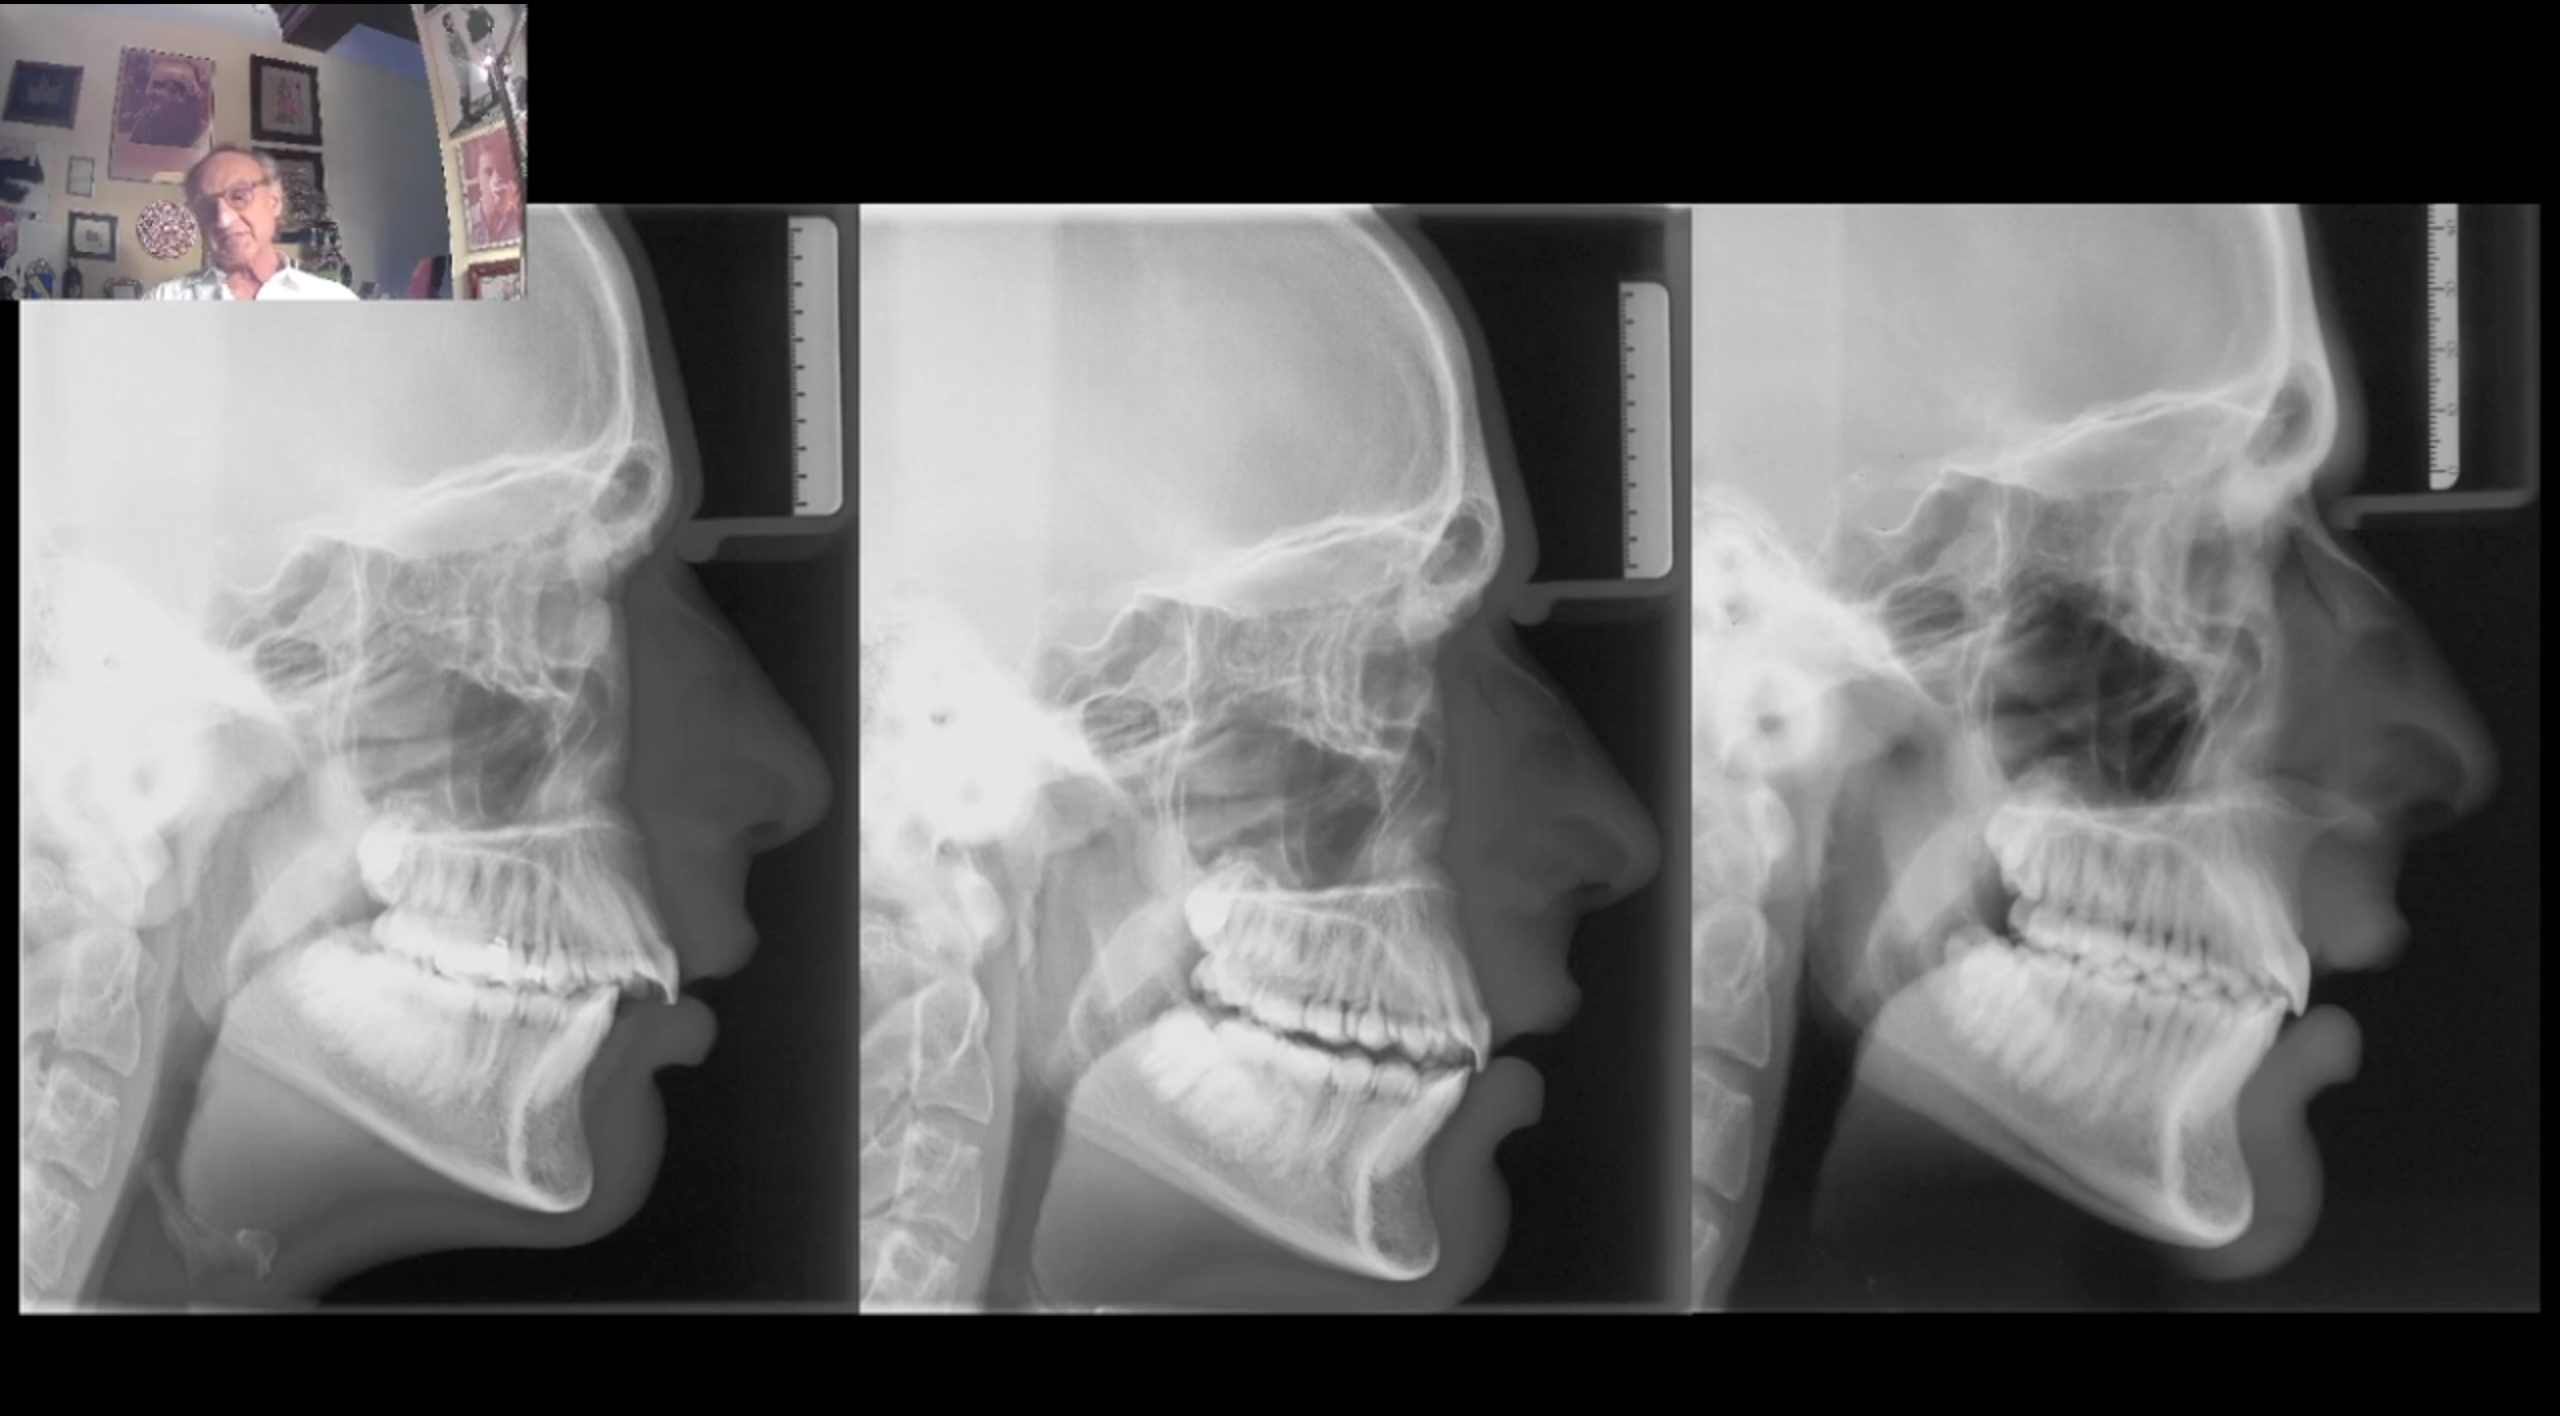

L’apparecchio di Herbst rappresenta attualmente il “gold standard” nel trattamento delle malocclusioni di classe II.

- La documentazione indispensabile per poterlo usare

- Il timing corretto